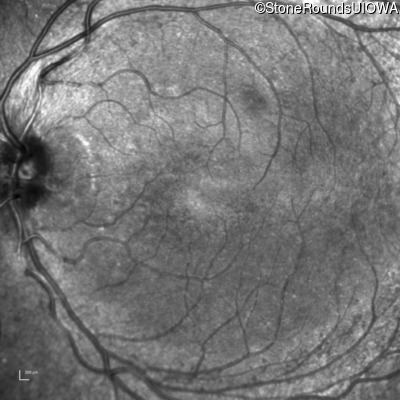

Infrared Fundus Photograph - Right - 20/25 -1

Exemplar